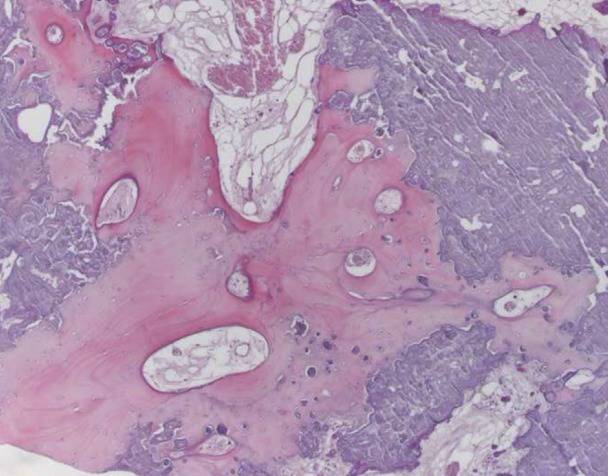

病理结果:化生型脑膜瘤,内可见基质钙化和不规则骨小梁形成。